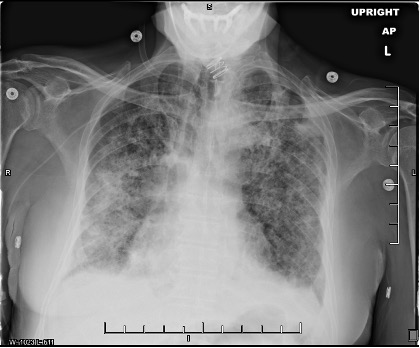

Reassessment of the patient’s presentation and findings resulted in a differential diagnosis of cryptogenic organizing pneumonia (COP). The patient was given intravenous methylprednisolone, 1 mL/kg/d, and had significant improvement of his respiratory symptoms within 24 hours. Serial chest radiographs taken at follow-up demonstrated partial resolution of infiltrates compared with previous imaging studies (Figure 3).

Figure 3. Chest radiographs taken 1 week (a, top) and 2 weeks (b, bottom) after initiating intravenous glucocorticoid therapy. The patient had been extubated and demonstrated significant improvement of symptoms during this period.Discussion. COP is a rare idiopathic interstitial lung disease that requires surgical biopsy for confirmation.1,2 In scenarios in which a biopsy is unavailable and the patient is intubated—such as in our case—careful consideration is needed. Adverse effects of glucocorticoids in a critically ill patient include immunosuppression and increased risk for potentially fatal nosocomial infection.3 Trial therapy should be started only if other, more common diagnoses have been excluded and if imaging studies are consistent with COP or another inflammatory process, such as acute respiratory distress syndrome. Fortunately, in our case, radiograph and CT findings did feature lower lobe consolidation and infiltration described in other reports of COP.3,4 Once suspicion for COP is high, the patient should be consulted on the risks of surgical lung biopsy vs trial glucocorticoid therapy and be offered a choice in which step to take next.